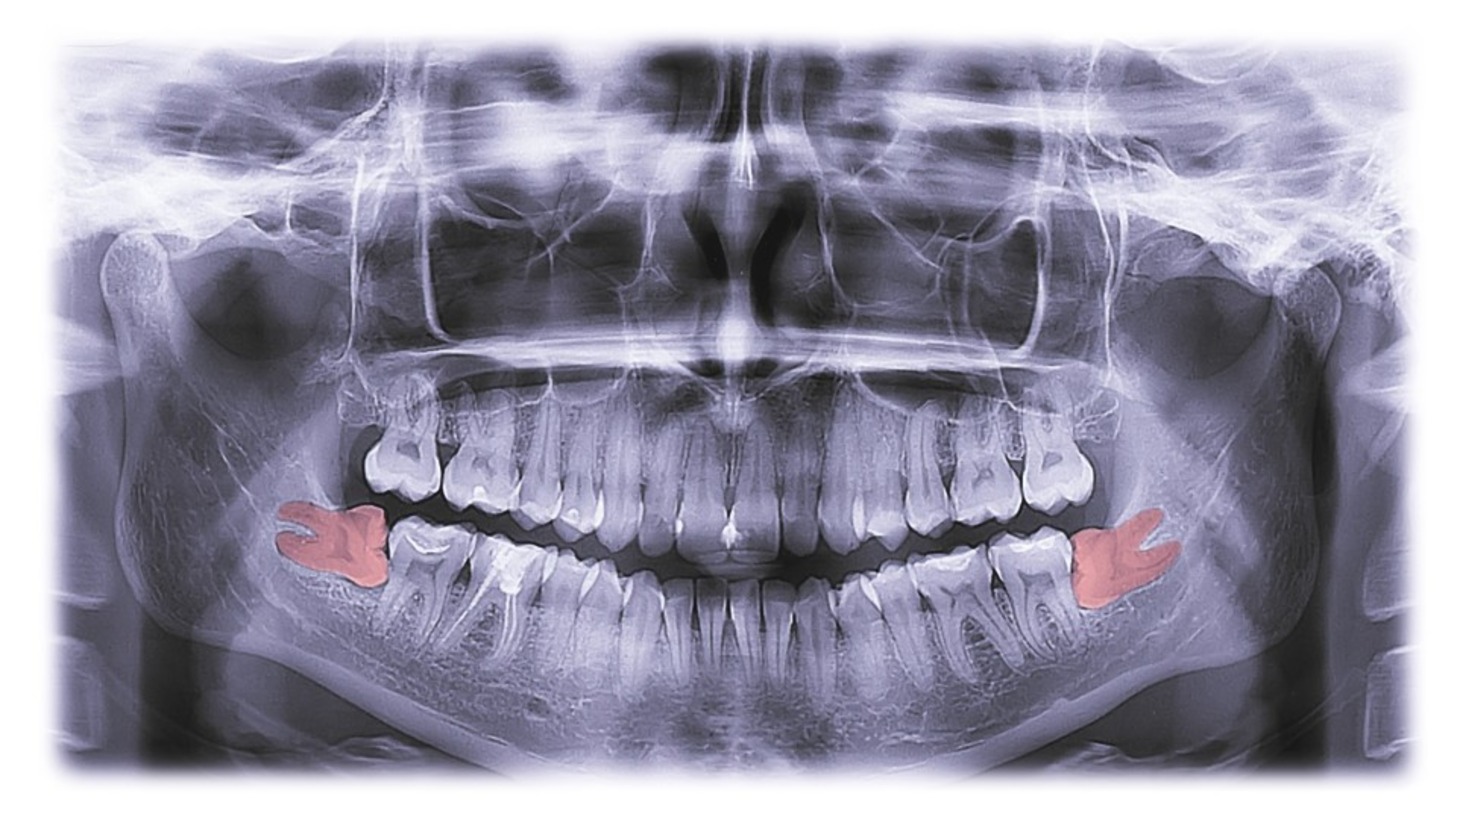

Wisdom Tooth Removal is a dental procedure designed to extract the third molars, commonly known as wisdom teeth, which often emerge between ages 17 and 24. These molars can cause issues such as impaction, infection, and misalignment due to insufficient space.

Why Do Dental Sealant

Wisdom tooth removal becomes necessary to address potential dental problems associated with impacted wisdom teeth. Impaction occurs when there isn't enough space for wisdom teeth to emerge properly, leading to pain, discomfort, and potential damage to adjacent teeth.

Removal of these problematic teeth is a proactive measure to prevent complications and maintain overall oral health. Additionally, it helps avoid issues like misalignment and infection caused by insufficient space. Wisdom tooth removal is a preventive and therapeutic procedure that contributes to a healthier and more comfortable oral environment.